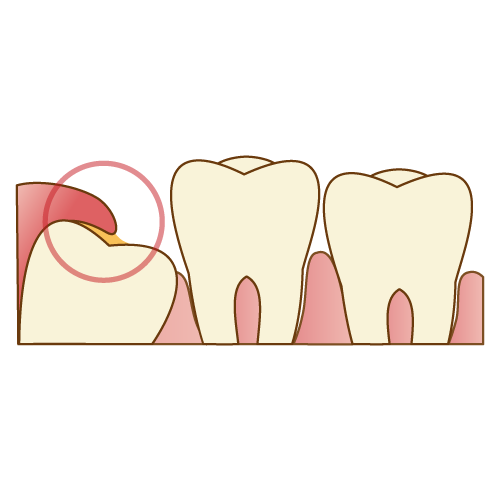

親知らずは歯茎が被さっていたり、親知らずと手前の歯の間の歯周ポケットが深くなってしまったりするケースが多く、歯磨きの際に歯ブラシの毛先が簡単に届かない事により汚れが残ってしまいます。これにより親知らず付近は細菌が繁殖しやすくなります。

多くの方が日頃から親知らず周りに自覚症状のない炎症を抱えており、このような自覚症状のない小さく継続した炎症を慢性炎症と呼びます。

通常の体調の時であれば、免疫力が細菌をコントロールし炎症を小さいままにしてくれますが、風邪の病み上がりや寝不足などにより免疫力が下がってしまうと、突然細菌達が強い炎症を引き起こし、歯茎が腫れて強い痛みを伴う急性炎症を引き起こします。このようなケースを炎症の急性化と呼びます。